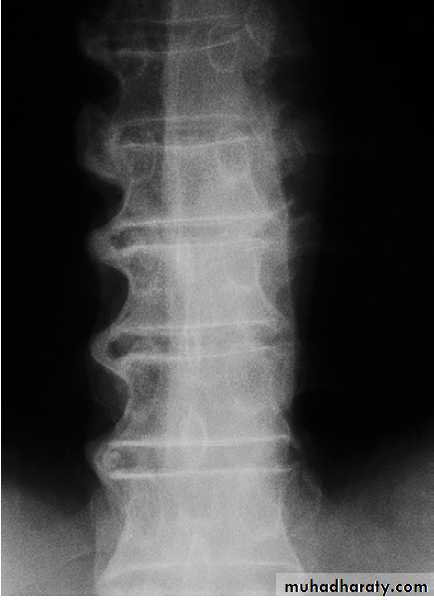

X-ray of spine showing typical changes of

osteoarthritis. Cervical spondylosis showing disc space narrowingbetween C6 and C7, osteophytes at the anterior vertebral body margins (arrows) and osteosclerosis at the apophyseal joints.